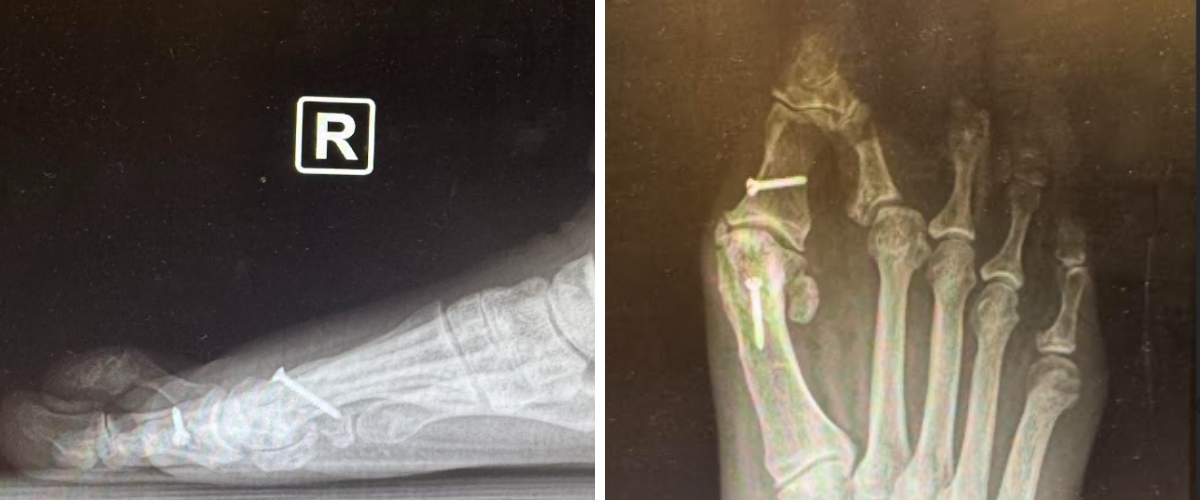

Oblique Metatarsal Osteotomy

For patients with transverse-plane deformity—including crossover toes, digital overlap, or windswept deformities—we prefer an oblique style osteotomy. This technique enables simultaneous shortening and medial or lateral translation of the metatarsal head, thereby improving tendon balance and MTPJ alignment.

After freeing the capital fragment, shortening can take place as needed, and the surgeon can adjust the sagittal plane position by plantarflexing or dorsiflexing the head. Frequent fluoroscopic evaluation helps confirm correction and alignment. As the capital fragment naturally translates proximally, it realigns the metatarsal phalangeal joint, reducing the tendon imbalance which can cause toe deformity. Fixation uses two snap-off screws placed perpendicular to the osteotomy. The surgeon should remodeling the distal metatarsal to eliminate any step-off distally. Soft tissue balancing and hammertoe correction can then take place as indicated, adding temporary MTPJ pinning if desired to enhance postoperative stability.

Indications

• Transverse-plane deformity requiring metatarsal head translation

• Digital overlap or MTPJ subluxation

• Combined deformity involving sagittal and transverse components

• Need for a forgiving osteotomy that permits fine-tuning of shortening and alignment

The oblique metatarsal osteotomy provides the versatility of simultaneous shortening and transverse-plane correction, making it ideal for deformities involving digital overlap, windswept toes, or combined MTPJ instability.